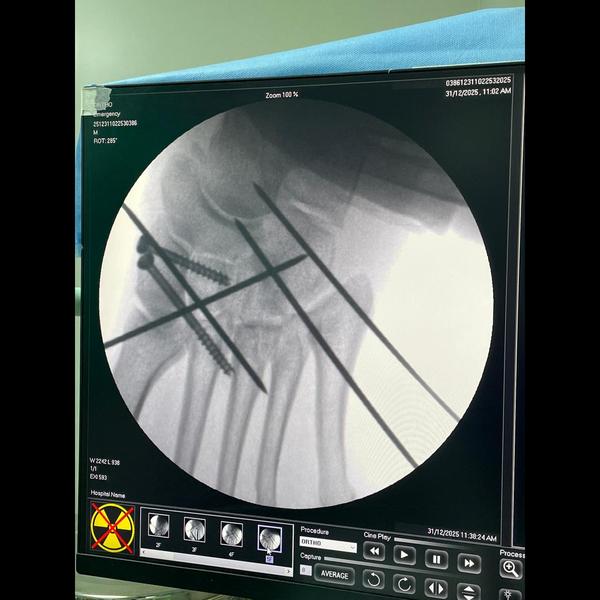

Lisfranc dislocation reduced completely !

Intraop Images !